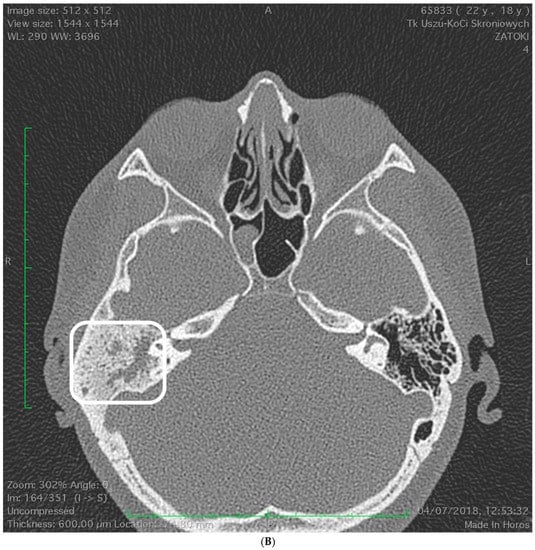

2.1. Case 1

2.2. Case 2

2.3. Case 3